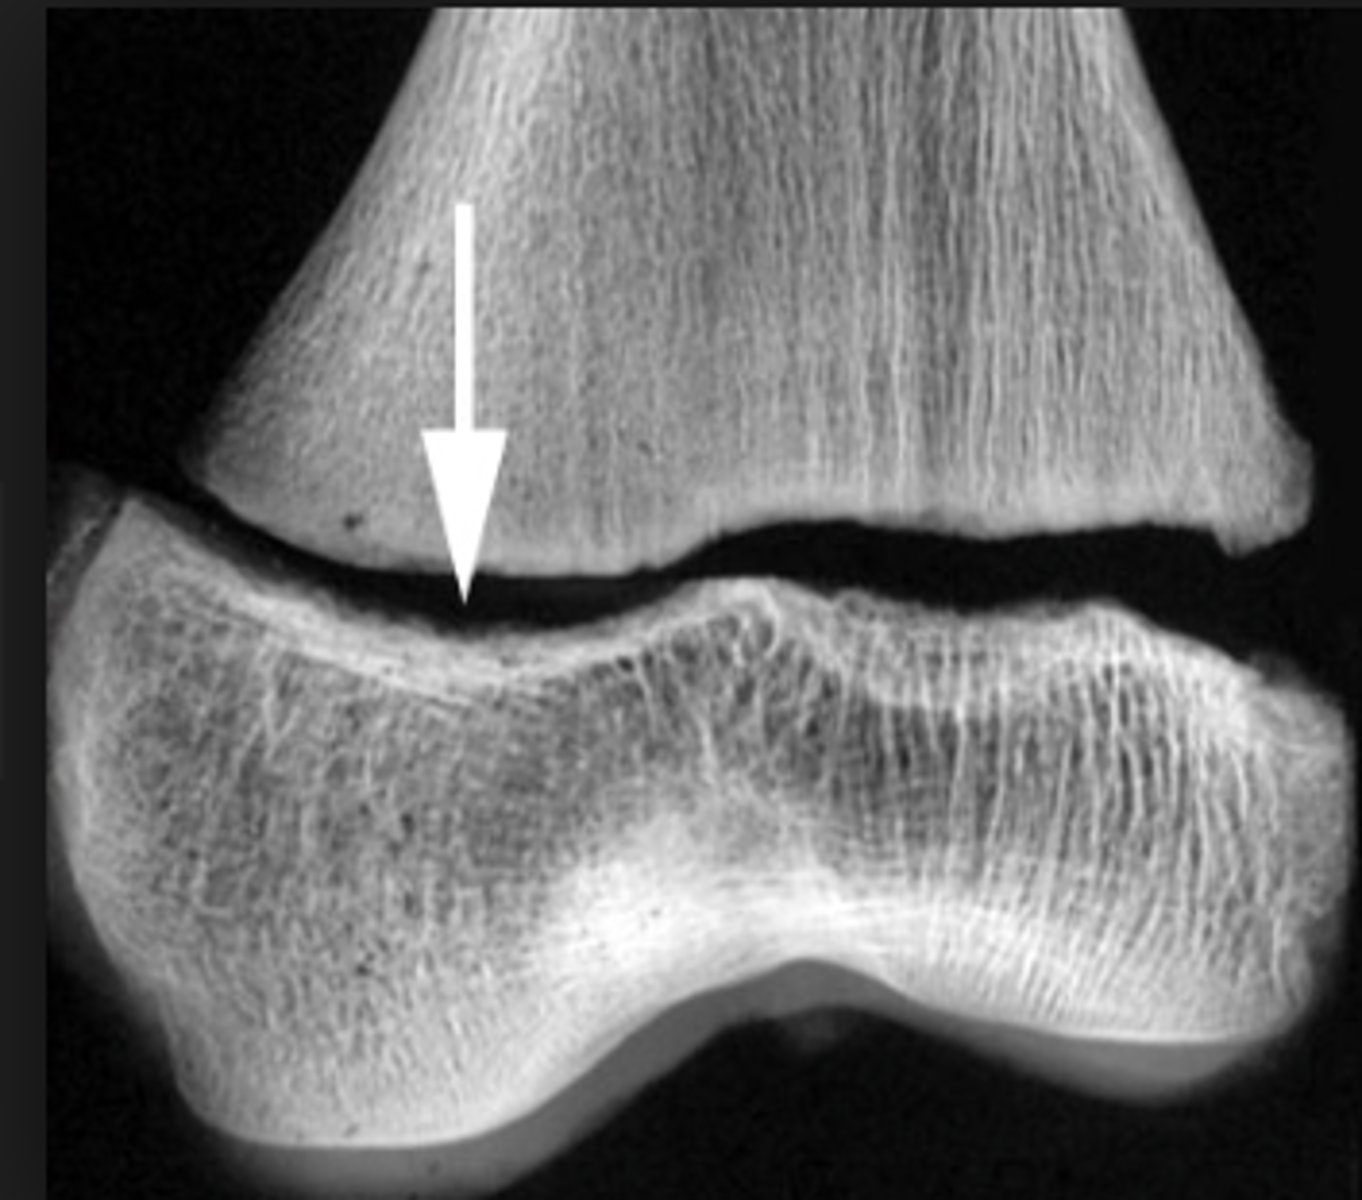

Salter Harris grade 1 growth plate fracture

Salter Harris grade?

Salter Harris grade 2 growth plate fracture

Salter Harris grade 3 growth plate fracture

Salter Harris grade 4 growth plate fracture

Salter Harris grade 5 growth plate fracture

Salter Harris grading scale

a system used to grade pediatric fractures that involve the growth plate (physis), categorized into Types I–V based on the injury's impact on the growth plate, metaphysis, and epiphysis